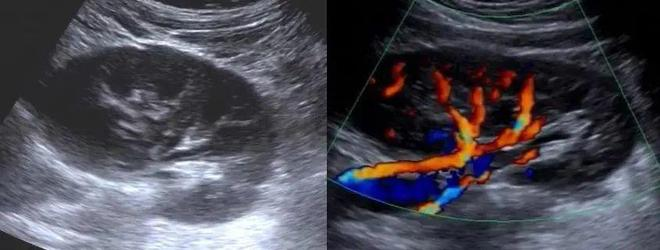

图2 肝内占位病变彩色多普勒图像